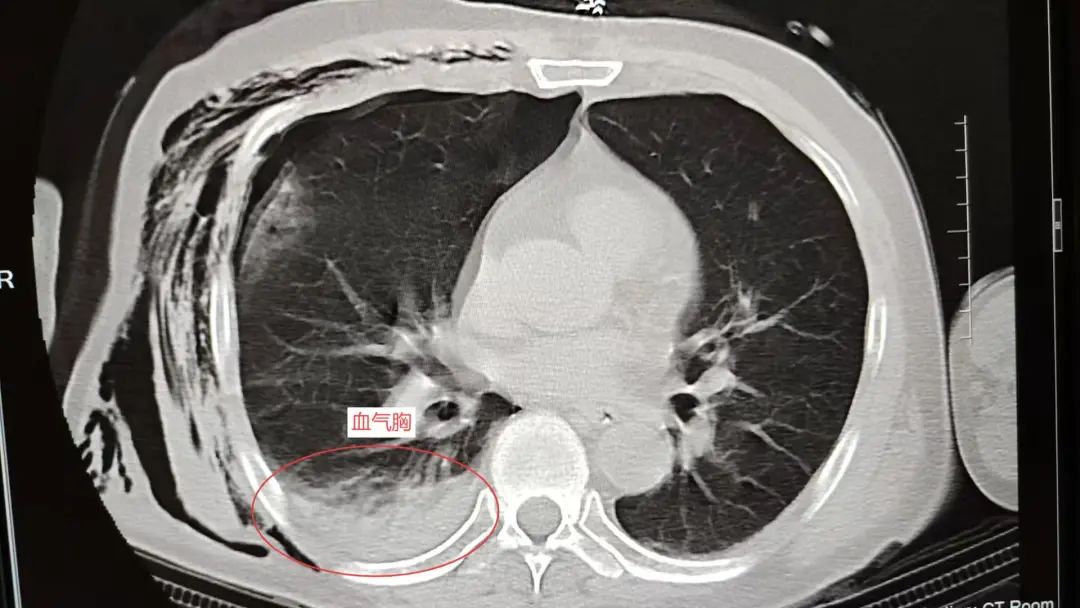

遭受严重创伤后,罗叔紧接着陷入昏迷。头皮血肿、血气胸、右胸腹部广泛的皮下气肿、血压持续降低等复杂危急症状接踵而至。这是一场与死神赛跑的硬仗,而留给和佳医院急救中心的时间以秒计数。

系统检查提示:罗叔目前存在车祸后多发伤,头部、胸部、腹部等存在多处外伤,颅脑的挫裂伤,右侧颌面部撕裂伤,右肘关节皮肤裂伤等全身多处皮肤擦伤。外表的伤口已经足够狰狞,而在罗叔的身体内部存在更严重的情况:闭合性颅脑损伤、呼吸衰竭、右侧6根肋骨骨折伴血气胸和皮下气肿、代谢性酸中毒、呼吸性碱中毒,还有肝、肺挫伤等脏器损伤。

当天10:12,在发现罗叔右侧液气胸加重,并出现呼吸困难,血氧下降情况时,团队迅速响应,进行右侧胸腔闭式引流+右侧皮下气肿引流。

两小时后的血气胸